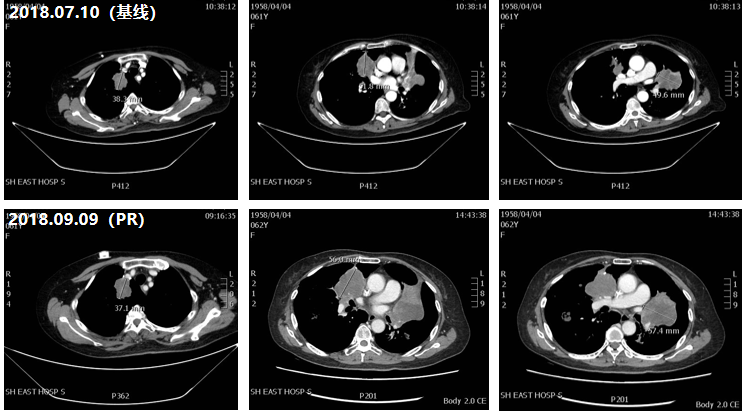

二线治疗(2019年7月——2020年8月)

治疗评估:考虑肺转移病灶引起阻塞性肺炎的可能,为减轻患者胸闷、气促的症状,二线治疗建议患者继续行“强化疗”方案,由于患者在既往化疗中有严重的胃肠道反应,强烈拒绝化疗方案;

治疗方案:口服呋喹替尼治疗;

疗效评估:患者口服呋喹替尼后,肺部及肝脏的病灶缩小,后病灶缓慢增大,共获得13个月无进展生存期(PFS)。直至2020年8月双肺病灶出现增多增大,肝脏出现新发病灶,提示PD;

图2 二线治疗CT影像对比